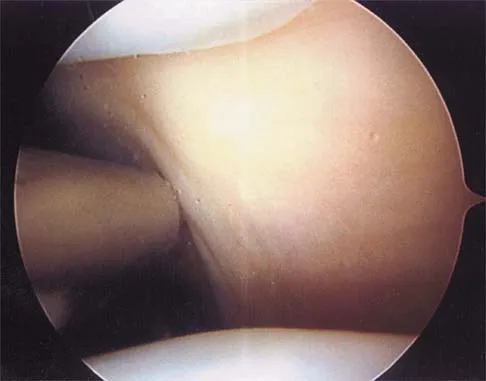

Based on the MR arthrogram of the elbow shown in Figure 8, which of the following structures is torn?